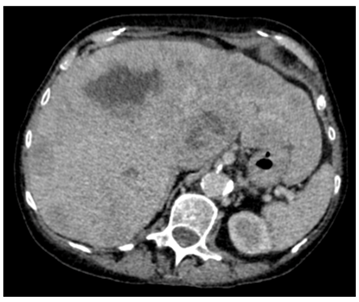

Our patient was a 79-year old female with severe progressive chronic obstructive pulmonary disease (COPD) on home oxygen, type 2 diabetes, hypertension and angina. She presented with type 1 respiratory failure and chest pain in December 2015. A computed tomography pulmonary angiogram (CTPA)4 months prior to this admission, showed no pulmonary embolism but did show a solitary liver lesion (Figure 1), measuring 2.5cm x 2.8cm that was suspicious for metastasis. A subsequent contrast-enhanced staging CT abdomen and pelvis demonstrated multiple liver metastases (Figure 2) with a 5.5cm solid-cystic lesion arising from her left kidney. After discussion with the Hepatobiliary multidisciplinary team (MDT), she underwent a percutaneous biopsy of the liver lesions, which showed metastatic carcinoma of indeterminate primary. She was seen by our Oncologists and was deemed suitable only for palliative treatment at this stage due to a presumed metastatic renal cancer and her multiple co-morbidities.

Figure 2: Staging CT chest abdomen and pelvis showing multiple liver metastases in December 2015.